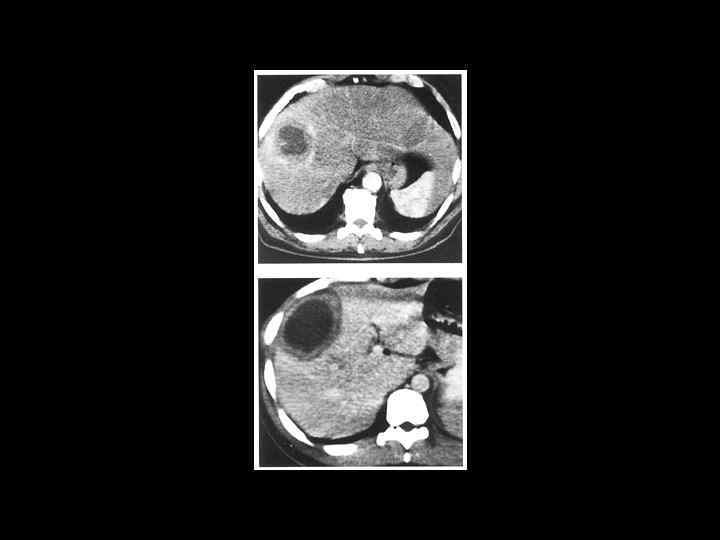

АКТУАЛЬНЫЕ ВОПРОСЫ РЕНТГЕНОЛОГИИ ЛУЧЕВАЯ ДИАГНОСТИКА ОЧАГОВЫХ ПОРАЖЕНИЙ ПЕЧЕНИ КАВЕРНОЗНАЯ ГЕМАНГИОМА Компьютерно-томографическая семиотика: - ограниченный участок пониженой плотности (до 50 -30 ед Н) - границы могут быть ровными, но нечеткими - после введения РКВ - характерный феномен усиления плотности от периферии к центру в течении нескольких минут после внутривенного введения РКВ

Клиническое наблюдение. Пациентка С. , 1953 г. р.

Та же пациентка